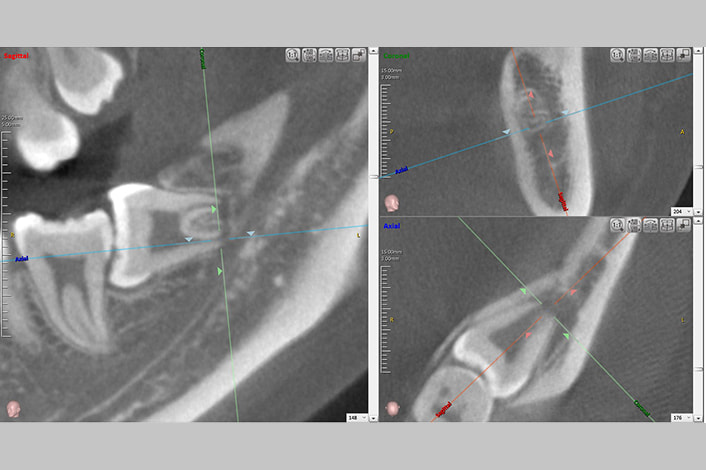

当院ではCT撮影を行い、親知らずの位置や神経との関係を正確に把握したうえで、抜歯の可否を判断します。

そのため当院では、矯正治療を安全かつ確実に行うために、CTで親知らずの位置や神経との関係を確認したうえで、抜歯の必要性を判断しています。

CT画像をもとに、抜歯によるメリットとデメリットを丁寧に比較し、将来的なリスクも含めて最適な方針をご説明します。

当院ではCTで位置や周囲の状態を確認し、抜歯の必要性を正確に判断します。

骨に埋まっている場合でも、CTで正確に位置を把握したうえで計画的に行うため、処置時間は最小限に抑えられます。

当院ではCT撮影で親知らずの位置と神経の走行を確認し、最適な時期と方法を判断します。